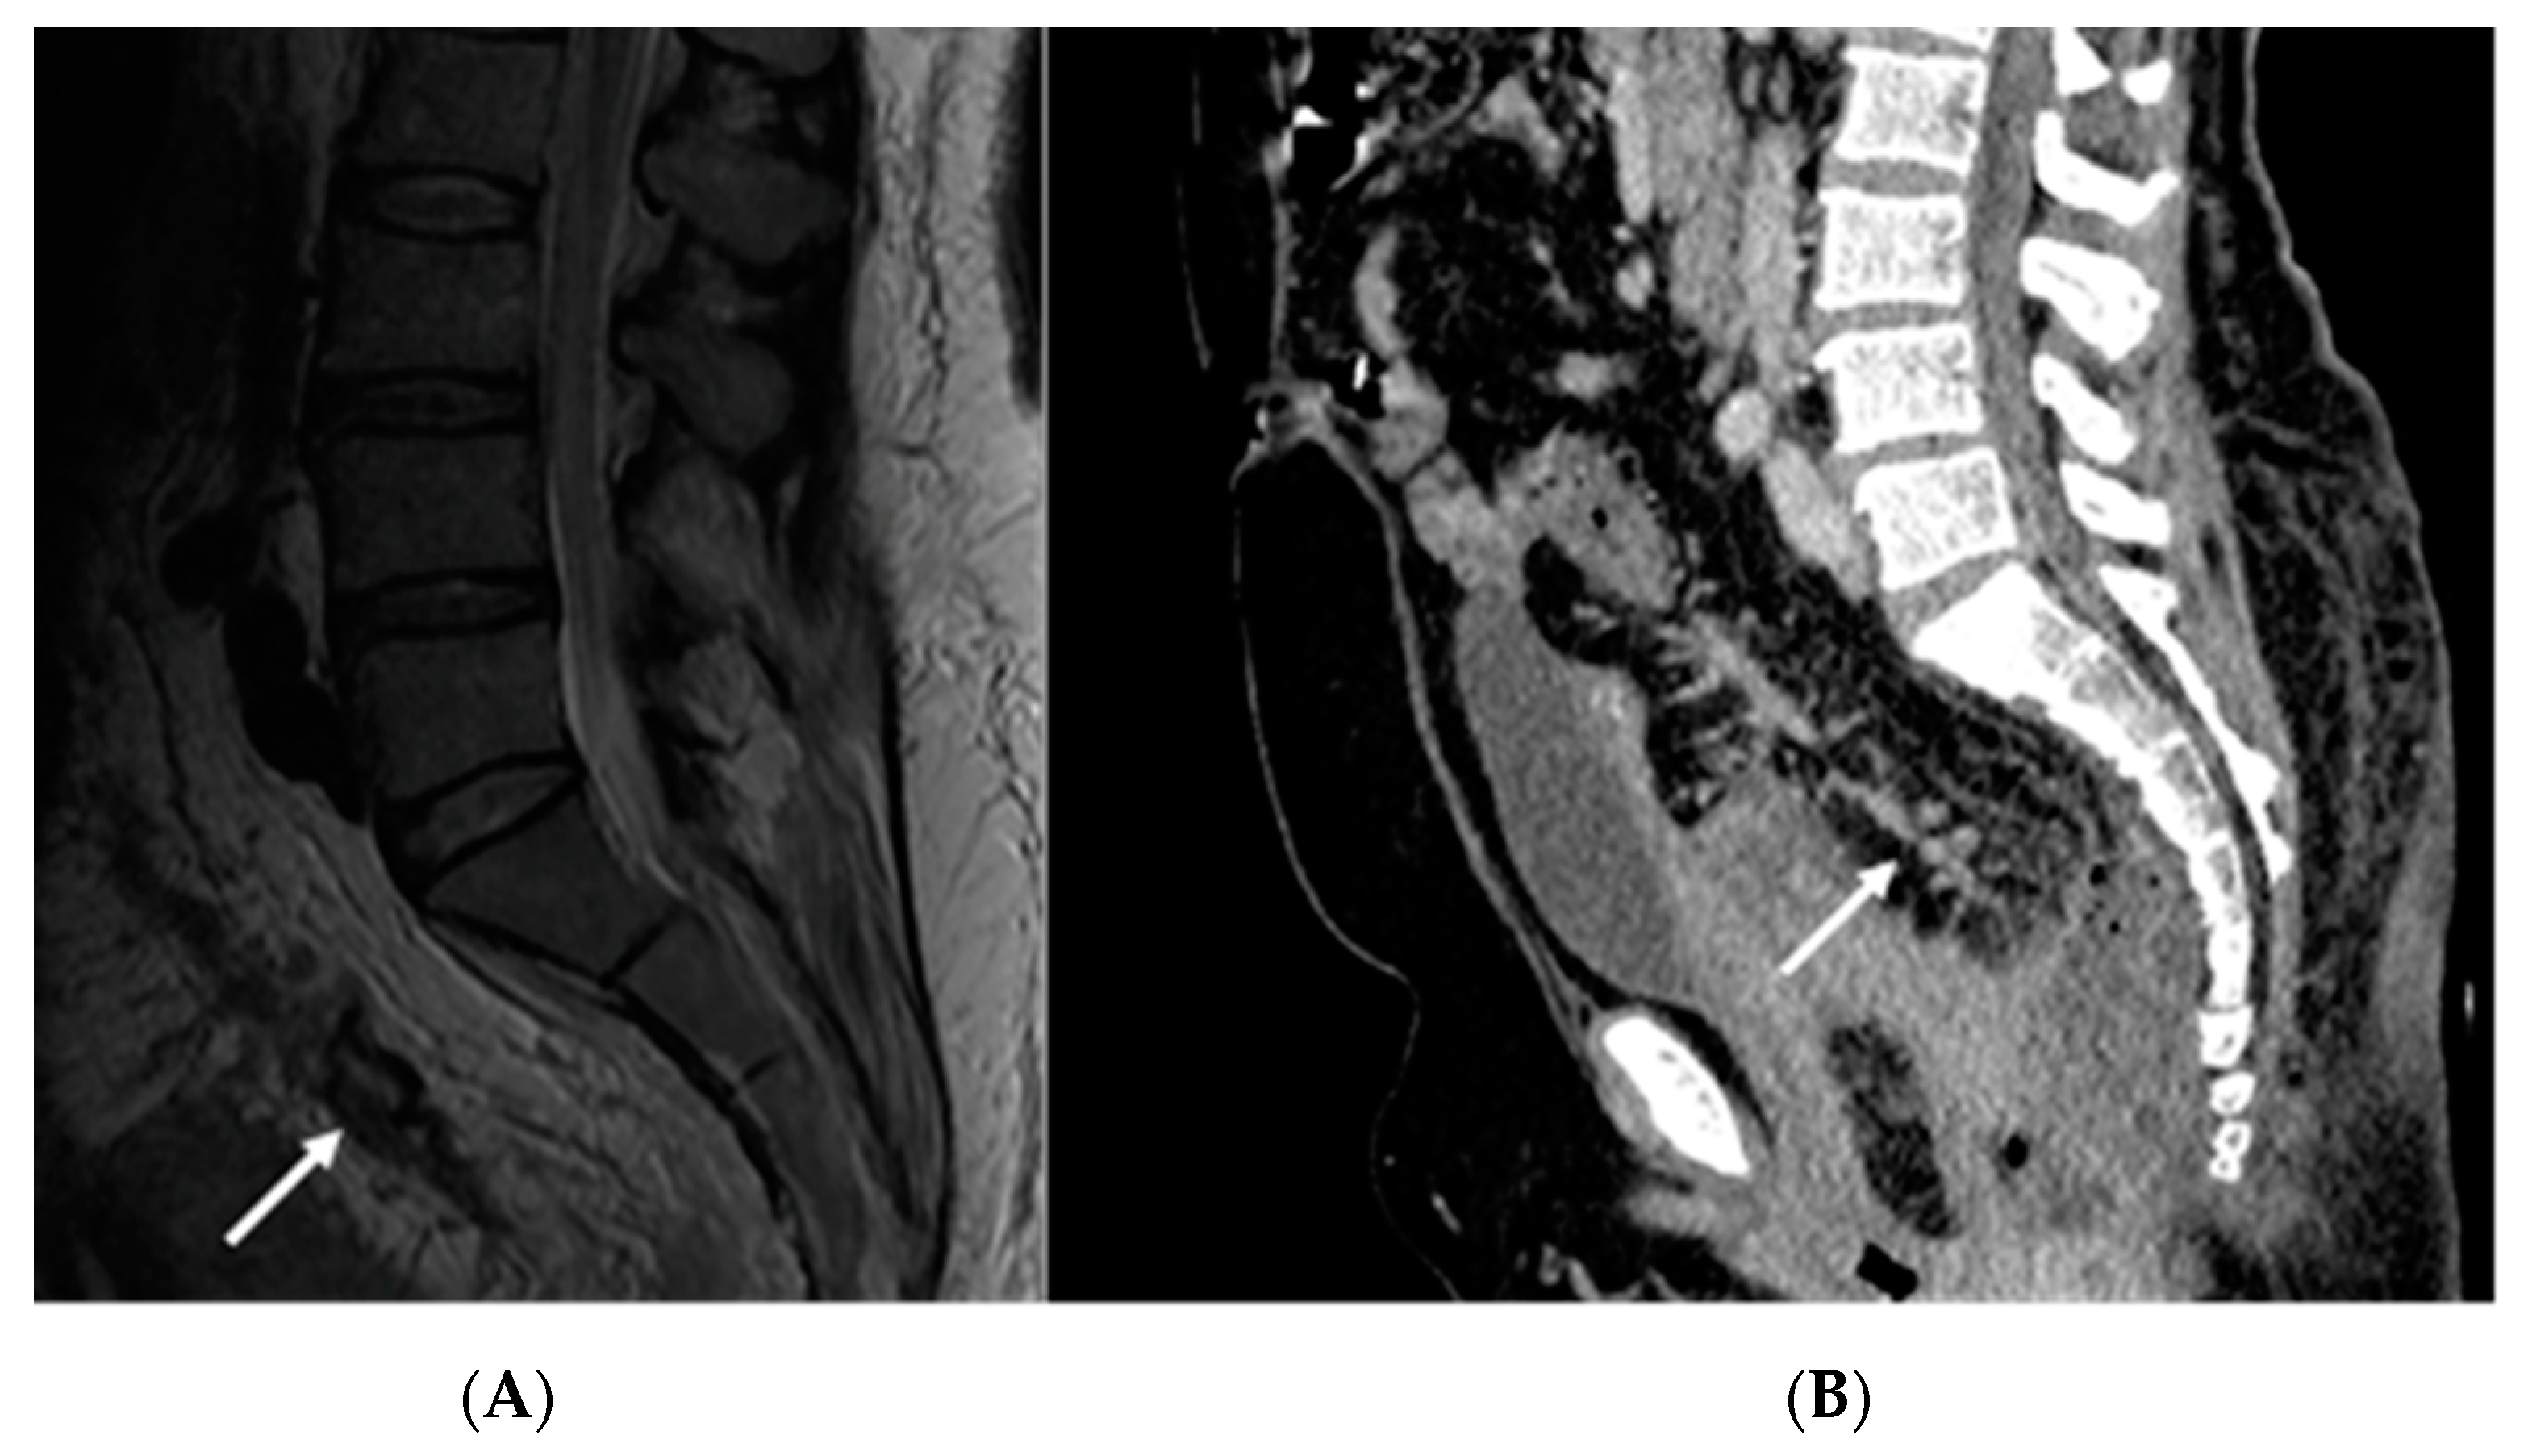

2.1. Case Report